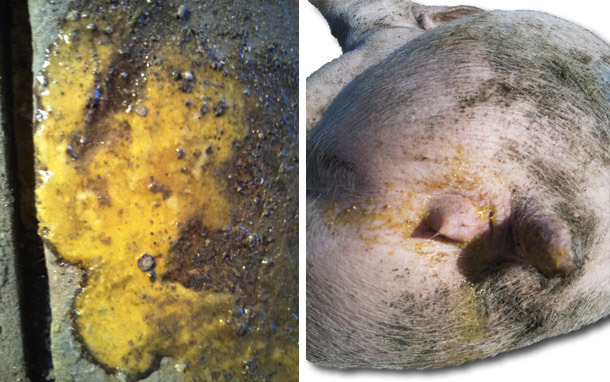

- Diarreias amareladas com presença de fibrina.

- Um deles com sangue coagulado nas fezes, apresenta icterícia.

Lesões. Em porcos com quadro agudo (necropsia a um porco afectado e sacrificado com pentotal sódico).

- Lesões macroscópicas.

- Engrossamento da mucosa na parte distal do intestino delgado (íleon terminal). Que se apresenta rígida e observa-se através da serosa.

- Ileite proliferativa na zona próxima à válvula ileocecal. Mucosa húmida com rugas e muito engrossada.

- Presença de vilosidades ligeramente aderidas.

- Gânglios linfáticos mesentéricos aumentados.